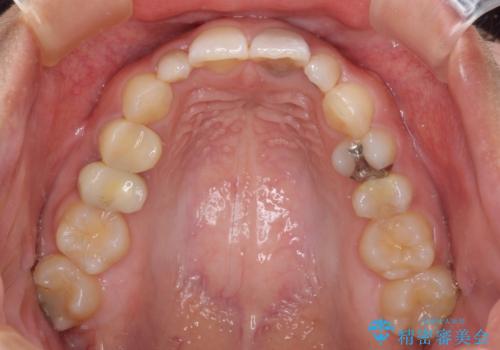

- 下顎の歯列から飛び出した小臼歯を気にして来院された患者様です。

歯列以外に、上顎左右側切歯が矮小歯であり、上顎4前歯は失活していたため、矯正治療で歯列を整えるとともに上顎前歯の幅を調整し、矯正治療後にオールセラミッククラウンにて審美歯科治療を行うこととしました。

矯正治療は、小臼歯1本分を歯列に納めないいけない状態であったため、表側のワイヤー装置にて行うこととしました。